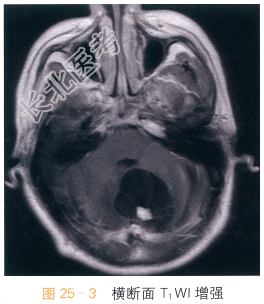

影像学资料如图25-1~图25-4所示。

读片分析:头颅横断面T₁WI示小脑半球囊性占位,呈低信号影,边界清晰,边缘光整,内可见附壁结节,呈等低信号影,第四脑室受压改变;横断面T₂WI囊液呈脑脊液样高信号影;增强扫描可见附壁结节明显强化。结合病史,患者考虑为血管母细胞瘤。